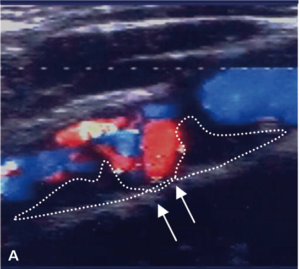

Badaniem ultrasonograficznym można uwidocznić zwężenie i ocenić jego morfologię.

Morfologia zmiany miażdżycowej nie stanowi według standardów kryterium kwalifikacyjnego do rewaskularyzacji, ale wykazuje silny związek z ryzykiem udaru niedokrwiennego mózgu zarówno u chorych leczonych zachowawczo, jak i okołozabiegowego IS w czasie rewaskularyzacji [18].

Zmiany hipoechogeniczne to zmiany częściej lipidowe lub skrzepliny, zmiany izoechogeniczne to zmiany włókniste, a zmiany hiperechogeniczne zawierają zwapnienia.

Zmiany hipoechogeniczne (skrzeplina, lipidowa) są związane z dużym ryzykiem IS zarówno u chorych dotychczas bezobjawowych, jak i w trakcie CAS czy endarterektomii (carotid endarterectomy, CEA), bo łatwo je uruchomić i rozkruszyć, powodując zatory do tętnic mózgowych [18].